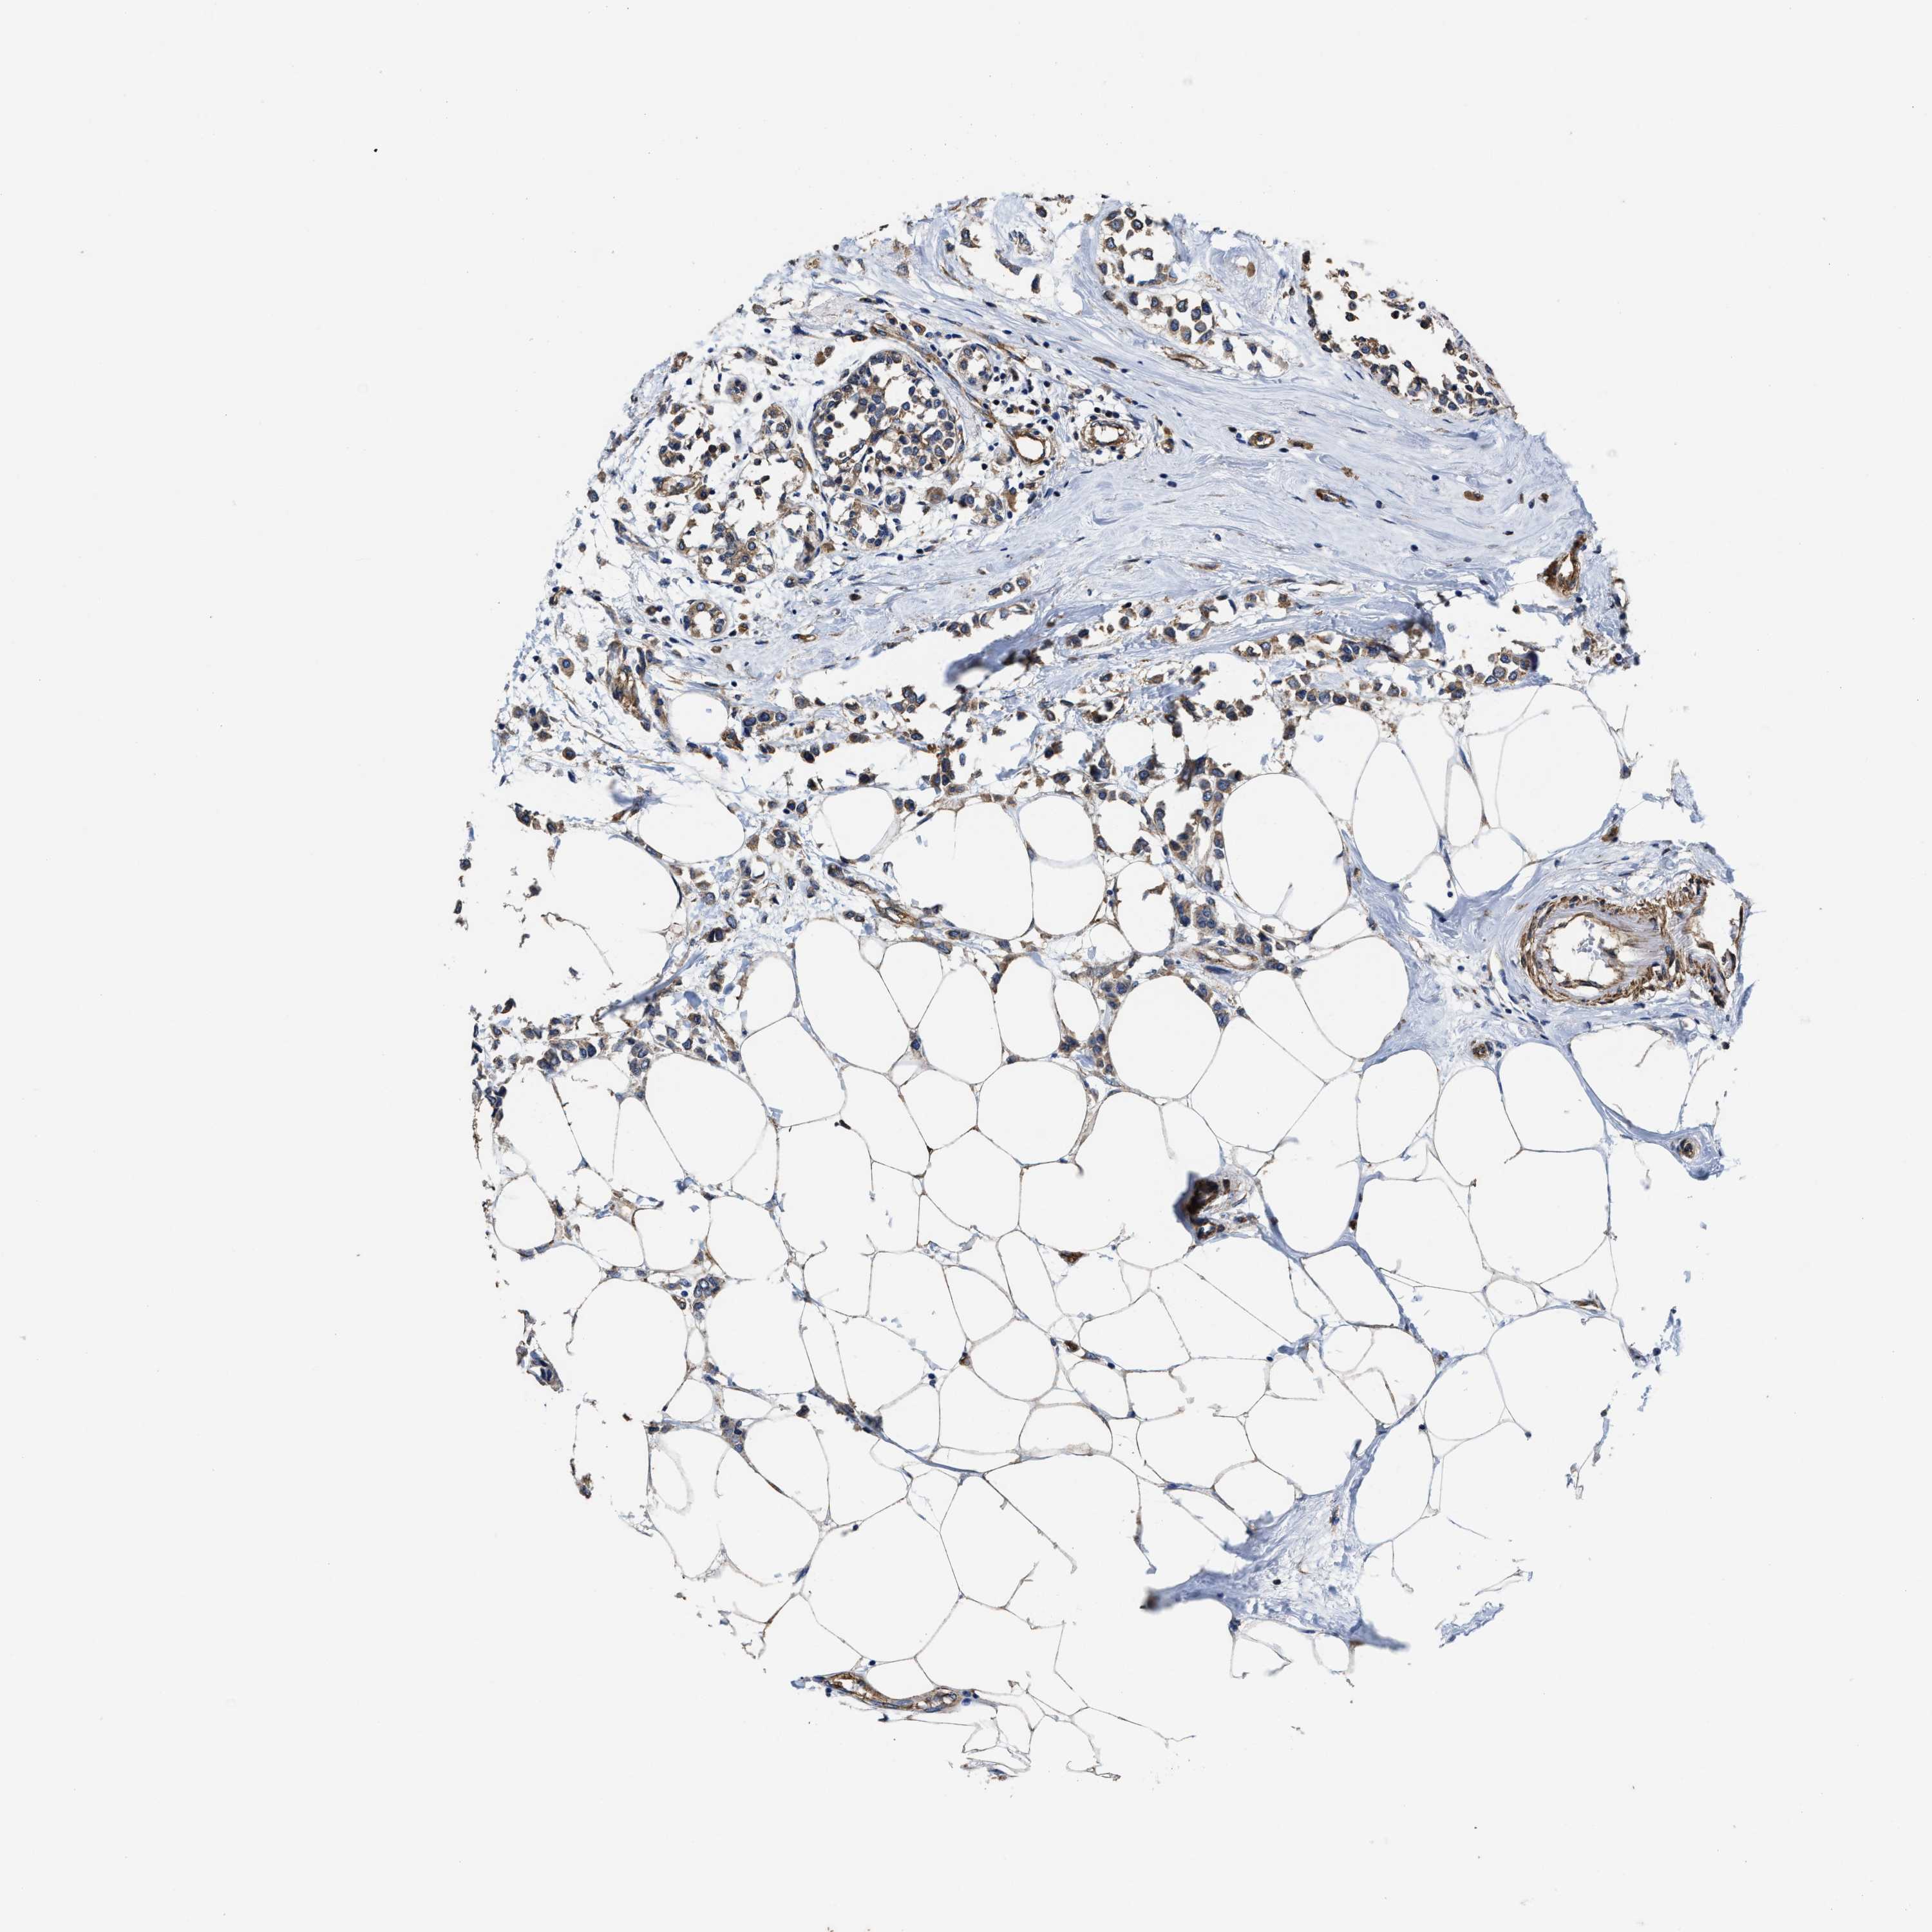

BRCA TCGA BRCA VALIDATION PROTEIN EXPRESSION

ANTIBODIES

AND

VALIDATION